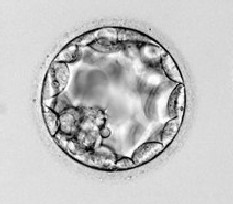

Ziua 5

Embrionul va deveni un blastocist prin formarea unei cavitati umplute cu

lichid.In acest stagiu,celulele se vor diferentia intre ele.Unele vor deveni

cele destinate formarii fatului(celule din interior,vazute ca un mic palc in

dreptul orei 7)si cele ce vor deveni placenta si membranele

amniotice.(tropectoderma si celulele perimetrice).

Ziua 6

Blastocitul va migra din zona pelucida pentru a se implanta in uter.Aceasta se

va intampla dupa ce embrionul a fost transferat in uter.